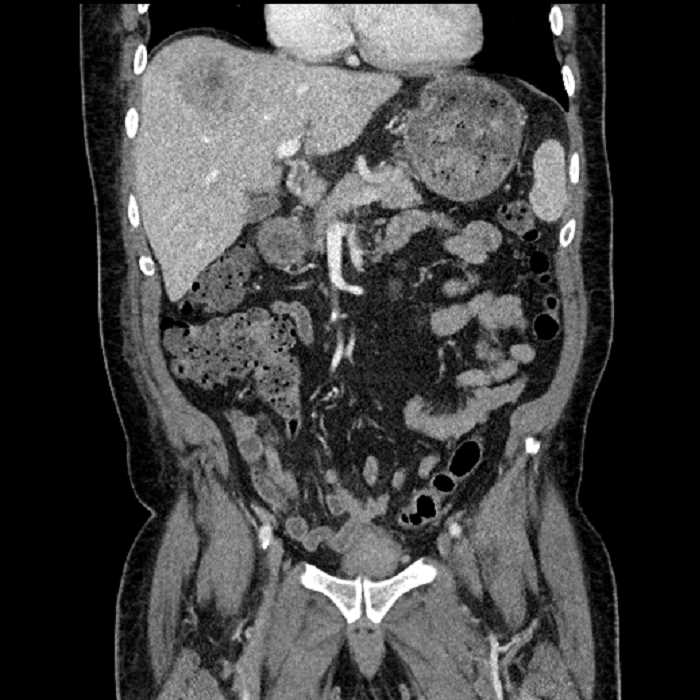

• Large fluid density structure in hepatic segments 7 and 8 measuring 10 x 7 x 7 cm with internal septation and circumferential ill-defined low density compatible with edema

• Peripherally enhancing subcapsular collections along the anterior margin of the left hepatic lobe measuring 3 x 1 cm and 2 x 1 cm

• Clearly marginated fluid density structure in segment 7 and several other scattered tiny hypodensities, which likely represent cysts

• Mild mural thickening of a segment of the sigmoid colon with adjacent fat stranding and a 1.5 cm fluid and gas collection along the tip of an inflamed diverticulum

• Loss of the normal fat plane between this collection and adjacent loops of small bowel, which demonstrate mural thickening

Acute sigmoid diverticulitis complicated by a small contained perforation and a large abscess in the right hepatic lobe. Additional small subcapsular abscesses along the anterior margin of the left hepatic lobe.

Additionally, loss of the normal fat plane between the peridiverticular collection and adjacent thickened loops of small bowel raises the potential for an enterocolonic fistula.

Hepatic abscess showing the double target sign with low density internally surrounded by a thin inner enhancing rim (red arrow) and ill-defined outer low density rim (yellow arrow). Blue arrow indicates an internal septation. Red arrows: additional smaller subcapsular abscesses. Red arrow: focal contained perforation associated with diverticulitis.